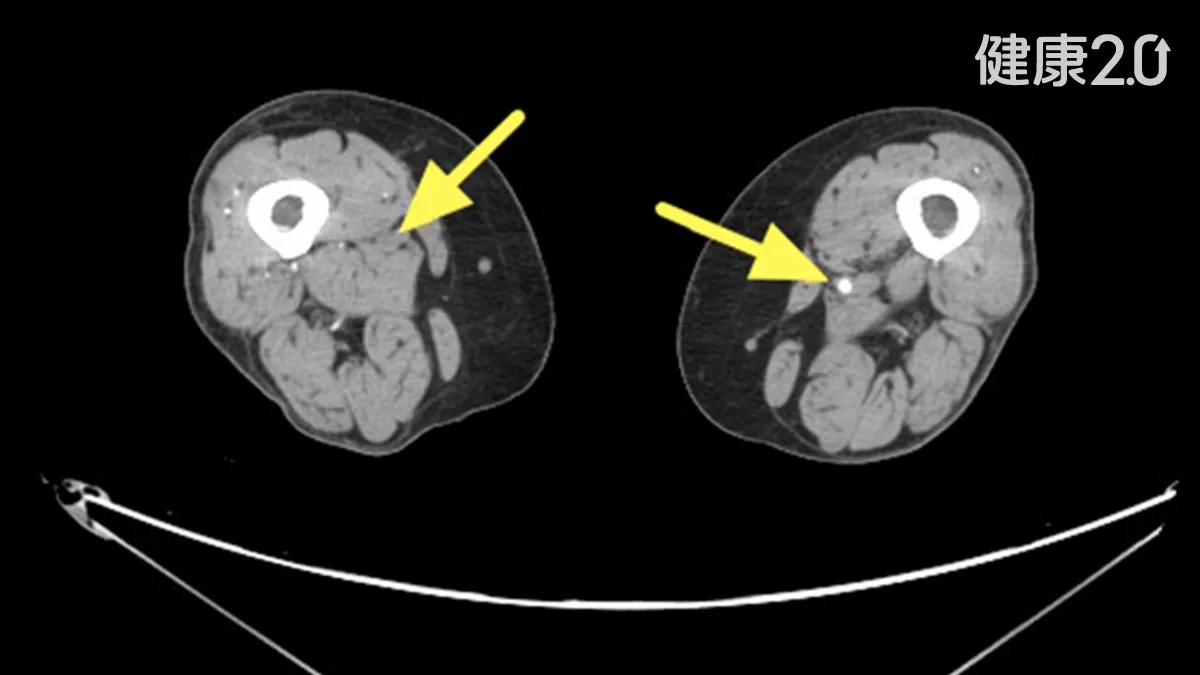

這名婦女就醫時,醫師檢查發現她右小腿與腳踝各有一處約3×5公分傷口,久久未癒合。整形外科醫師清創時更發現,這2處傷口幾乎沒有出血,於是轉介心臟血管外科,經踝臂血壓指數(ABI)檢查僅0.64至0.67,電腦斷層血管攝影顯示雙側股動脈與膕動脈嚴重狹窄。